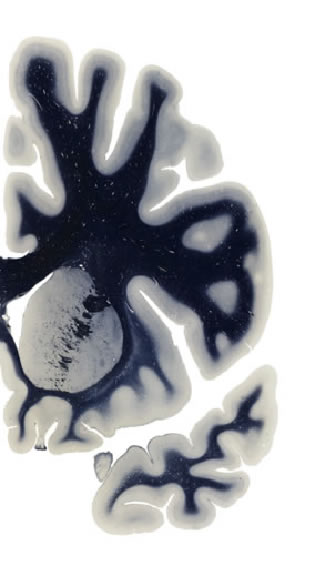

Hi-Resolution Sections · Cells (Nissl Staining) · Virtual Microscopy

Frontal sections (Nissl) from the Atlas Brain:

Slice ID:

r2-0307

Plate NR:

13

Position:

-12,5 mm